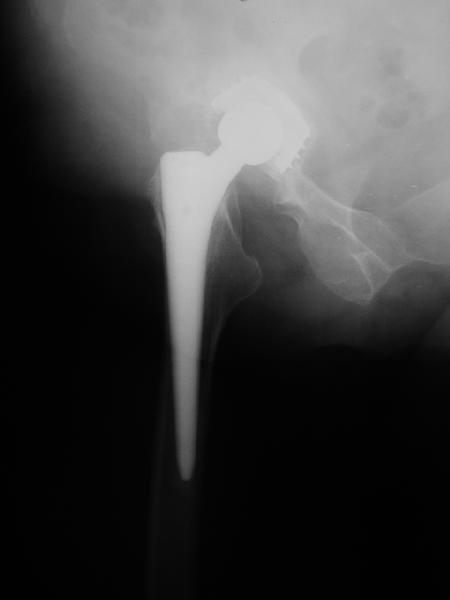

В наше отделение обратилась больная (родственница одного из сотрудников) 1948 г.р. В 2002 г. тотальное эндопротезирование тазобедренных суставов в Кургане.

Все было благополучно до 22 апреля этого года, когда при развороте на фиксированной стопе появилась резкая боль в правом тазобедренном суставе и верхней трети бедра. Конечность стала неопорной. Активные движения - резко болезненны. Пассивные - свободные, безболезненные. Местно - есть зона гиперемии в вертельной области. Пальпаторно - флуктуация (гематома?) по задне-наружной поверхности бедра. Температура субфебрильная. Больная сейчас на постельном режиме, двигаться, а тем более вставать отказывается из-за боли. Снимки прилагаются. Больная обращалась в клинику эндопротезирования Уральского НИИТО, ей было отказано даже в консультации.

Август 2002 г.

24 апреля 2005 г. правый сустав фас (тут и болит)

С выбором имплантата можно не согласиться, но скорее всего просто поставили то, что было в наличии. :( Вертлужный компонент установлен

слишком медиально. По представленным рентгенограммам нельзя исключить нарушение целостности дна вертлужной впадины. Даже если в данным момент нестабильности нет, то она обязательно возникнет и скорее всего, создаст

На представленных Р-граммах явных признаков нестабильности эндопротеза нет. Чашка хоть и медиализирована, но стоит так же, как и 3 года назад и остеолиза нет. Есть остеолиз вокруг проксималного отдела ножки, но линия тонкая и не захватывает дистальный отдел. Судя по клинике, можно думать о травме (отрыв) ягодичных мышц в